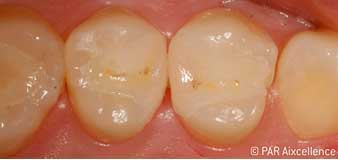

Рис. 9. Законченная долговременная реставрация